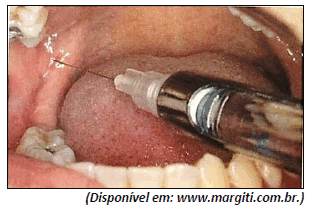

Analise a imagem a seguir.

Qual é a técnica de anestesia mostrada na figura anterior?